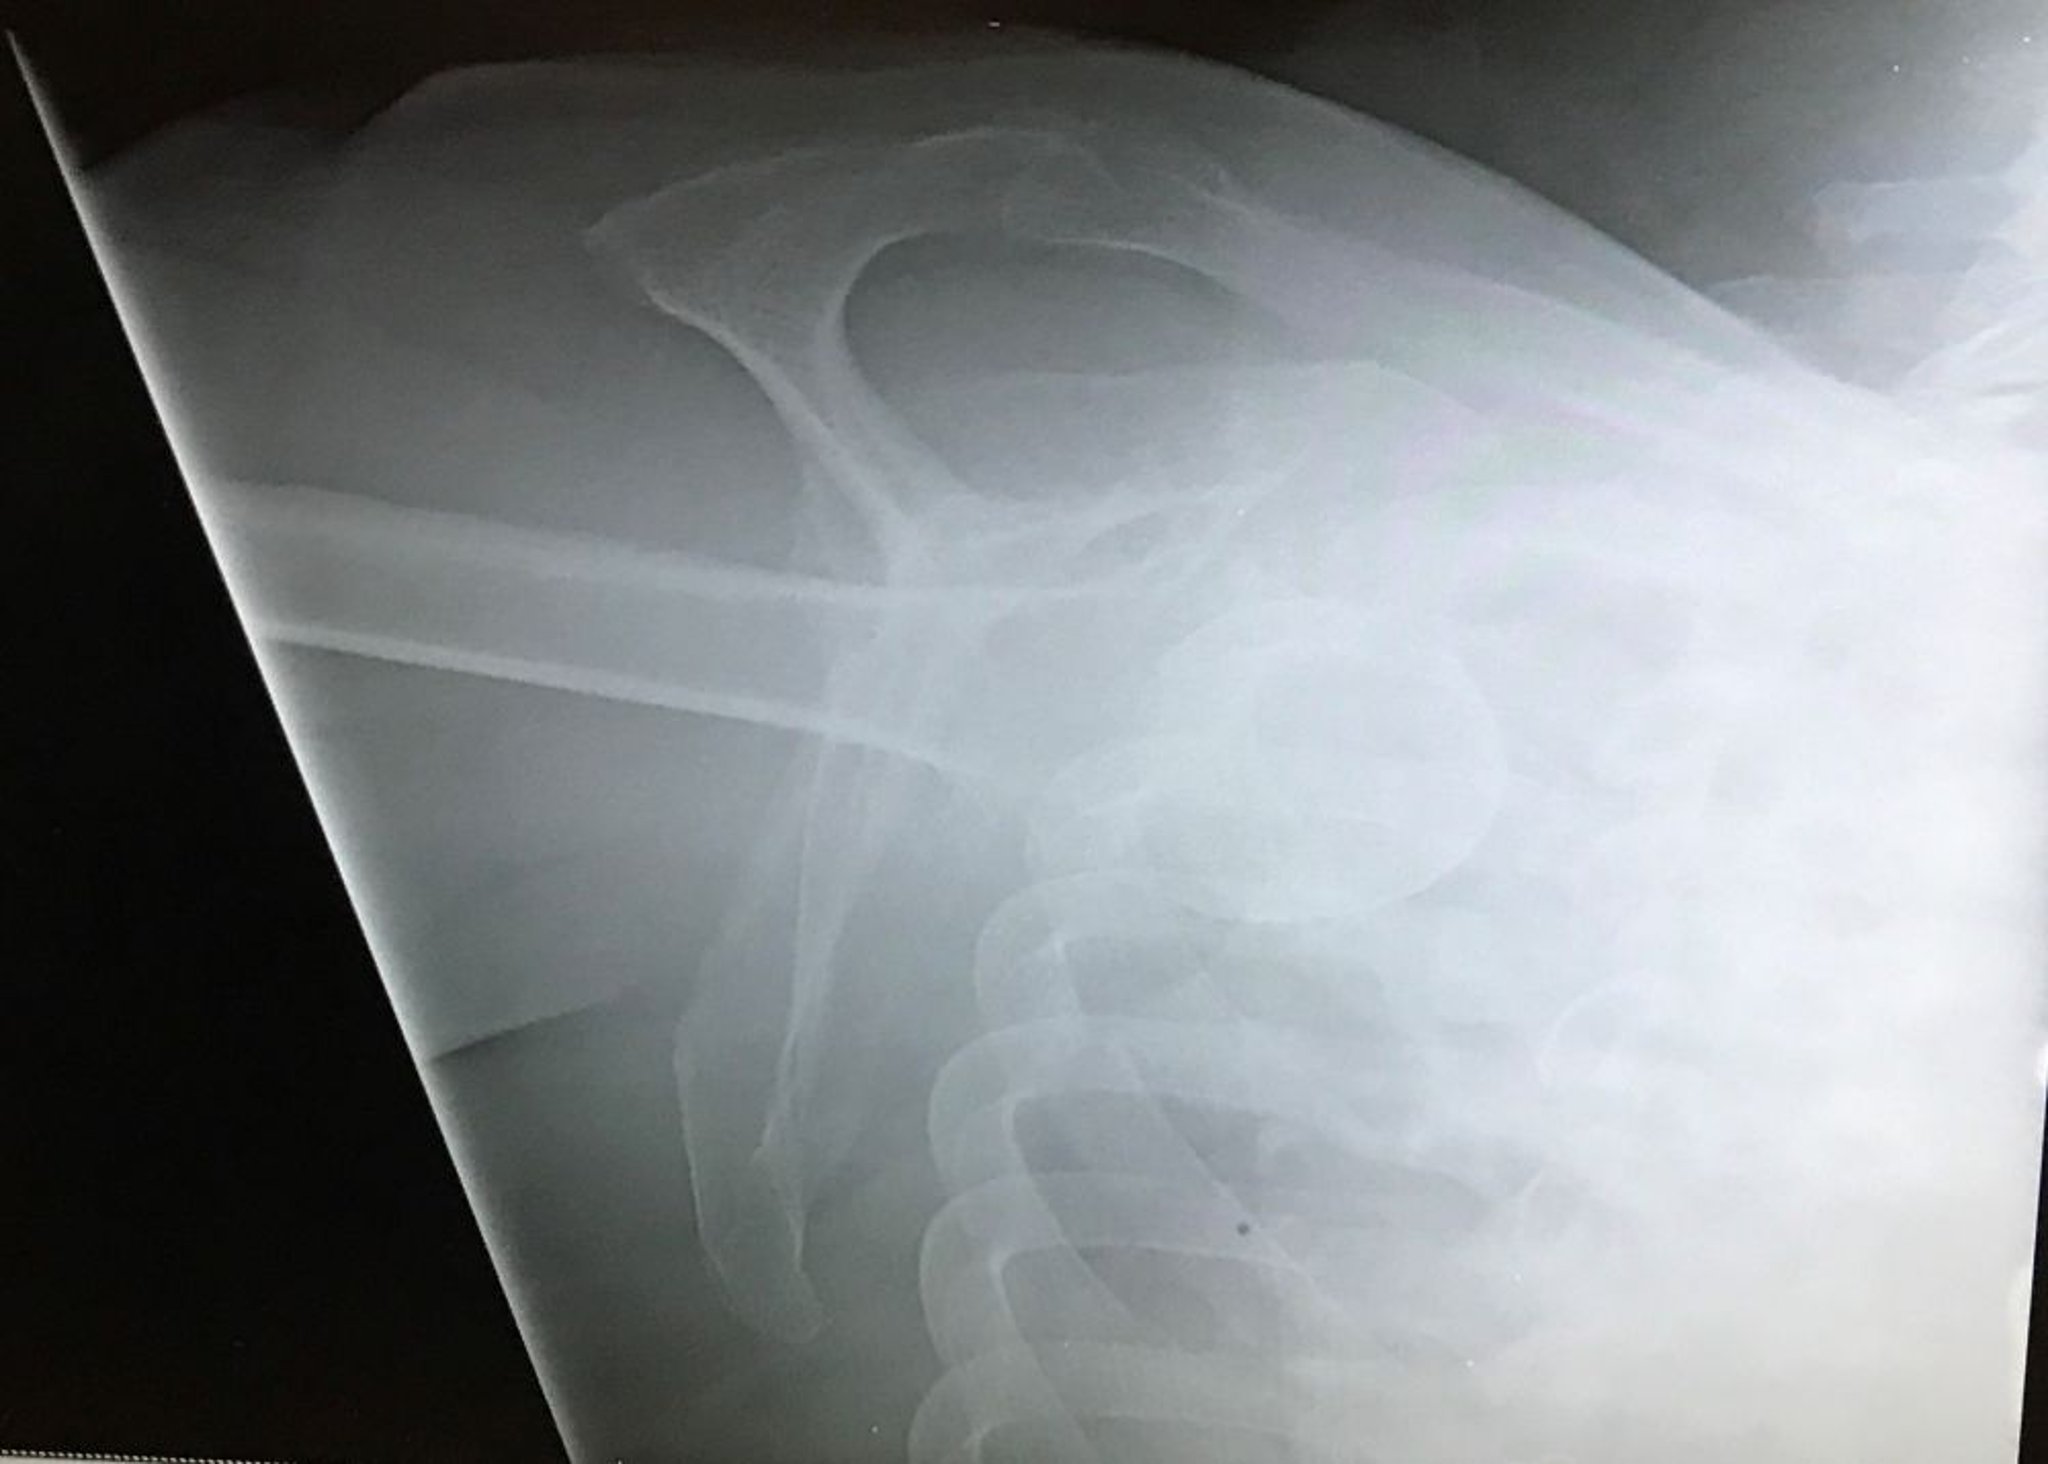

Trật khớp vai xuống dưới

Hình chữ Y này của vai cho thấy đầu xương cánh tay thấp hơn mỏm cùng với xương quai hàm, cho thấy trật khớp háng (lồi mắt).

Hình ảnh do bác sĩ Danielle Campagne cung cấp.